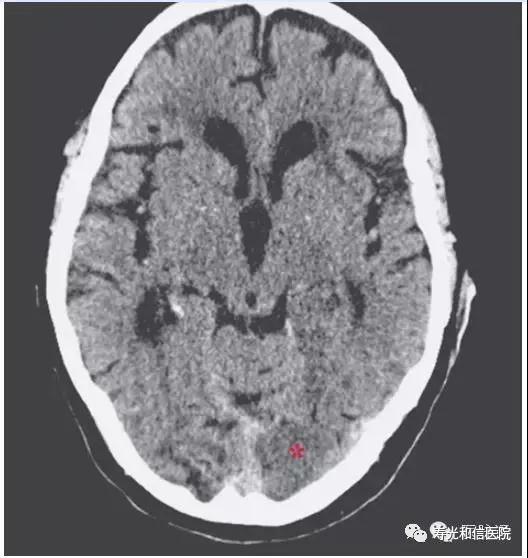

患者,男,84岁。既往有高血压、糖尿病和高脂血症病史,因视物异常6小时送入急诊室。查体发现右侧同向偏盲,无其他神经系统体征。此外,发现双侧耳垂斜向折痕——Frank’s征。

紧急头颅CT显示亚急性枕叶梗死(左侧大脑后动脉供血区),及多发陈旧性缺血灶(下图)。

患者后经保守治疗,病情平稳,1周后出院,有持久性的视野缺损。